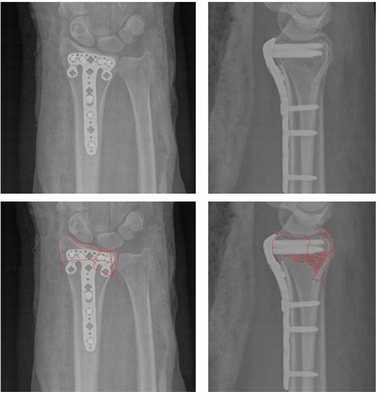

По этой причине в нашей клинике мы предпочитаем лечить такие типы переломов оперативно. Для фиксации данного типа повреждений предпочтительно использовать пластины с угловой стабильностью с дистальным расположением винтов, которые можно ввести субхондрально, ближе к суставной поверхности. В своей практике мы используем пластины фирмы Synthes - 2.4mm Variable Angle LCP® Volar Rim Distal Radius System.

Такой тип фиксации позволяет добиться стабилизации перелома, отказаться от гипсовой иммобилизации и начать раннюю разработку движений в лучезапястном суставе, что в конечном счёте приводит к отличным функциональным результатам. Оперативное вмешательство целесообразно проводить непосредственно в день травмы, до нарастания отёка, оптимально - в первые 6 часов после травмы.

Остеосинтез позволяет восстановить нормальную анатомию, утраченную при травме. Благодаря этому возможно правильное распределение нагрузки, и восстановление полного, безболезненного объёма движений. Риски хирургии минимальные, при должном знании анатомии повреждение сосудисто-нервных пучков, срединного и лучевого нерва. Практически исключено. Не стоит использовать слишком длинные винты. Так как они будут раздражать сухожилия на тыльной поверхности лучезапястного сустава и нижней трети предплечья. Для уменьшения риска КРБС, формирования синдрома карпального канала, следует бережно обращаться с тканями, использовать вакуумные дренажи, назначать в послеоперационном периоде препараты аскорбиновой кислоты.